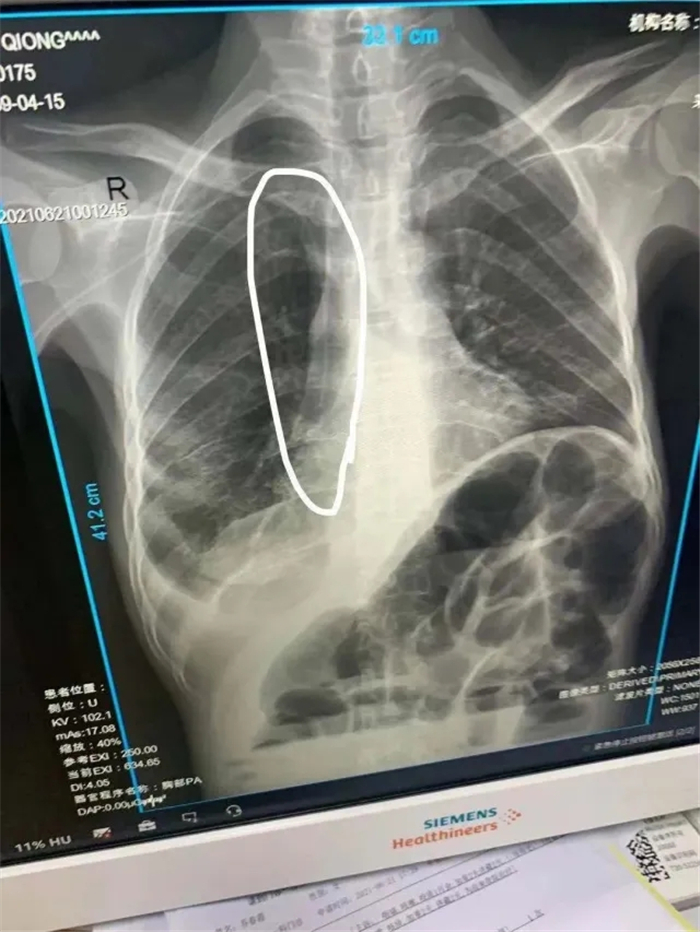

考慮到該患者左側(cè)貴要靜脈堵塞,因此術(shù)中選取右側(cè)貴要靜脈上段為最佳穿刺靜脈,沿靜脈走行達上腔靜脈,并通過拍片確定導(dǎo)管尖端位于上腔靜,固定導(dǎo)管,顯示導(dǎo)管無異常,PICC尖端位置較好,置管術(shù)順利完成。